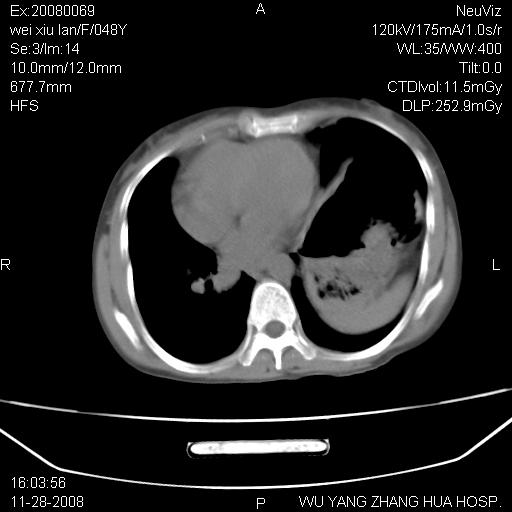

标题: CT16847:女,48岁,咳嗽,发热两日,平常偶有上腹部不适。 [打印本页]

标题: CT16847:女,48岁,咳嗽,发热两日,平常偶有上腹部不适。

能否考虑食管裂孔疝?请老师们多多指教。

支持左侧膈疝,心脏受压右移.

胃、脾脏及部分肠管明显升高,并压迫心脏移位,

首先考虑:左侧膈疝。

左侧胸腔内见胃肠及脾脏影

支持膈疝